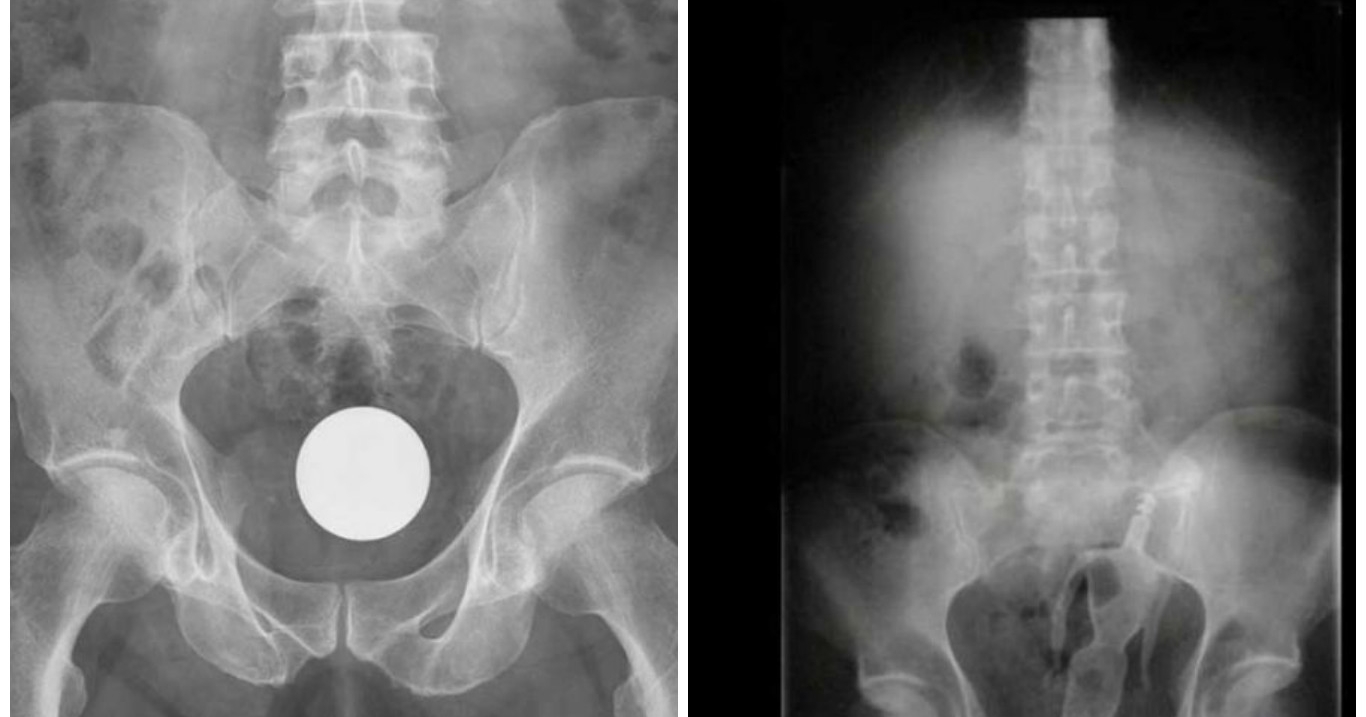

Quando o prazer vira um caso de emergência médica. Pessoas que se excederam e foram parar na emergência em função de objetos bizarros introduzidos no ânus. Confira.